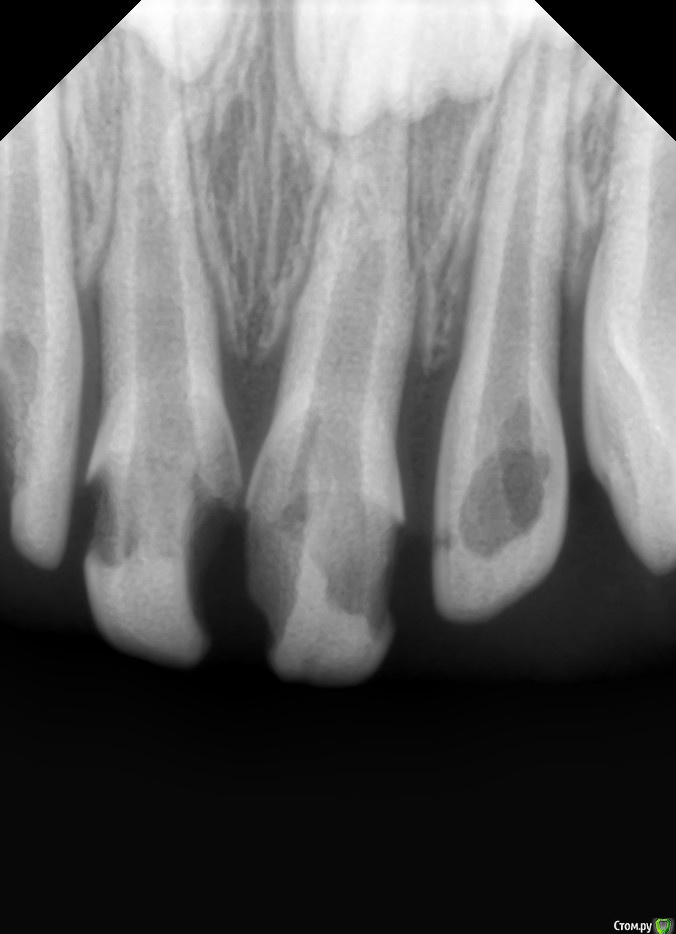

CRAZYDUCK Опубликовано 29 апреля, 2016 Поделиться Опубликовано 29 апреля, 2016 (изменено) Не смогла найти тему , в которой ЦОЭ обсуждали .Вот снимок до лечения (в ноябре )Девочке 3 годика ,договориться не удалось,отправила в другую клинику на сани с седацией ,полечились, пришли неделю назад с жалобой на подвижность зуба ,зуб реально ходуном ходит ,свища нет и вот он ЦОЭ ,даже с такой резорбцией не очень хочет рассасываться Но снимка после пломбирования у меня конечно же нет ,но боковой резец запломбирован хорошо . Изменено 29 апреля, 2016 пользователем CRAZYDUCK 2 Ссылка на комментарий

Джима Опубликовано 30 апреля, 2016 Поделиться Опубликовано 30 апреля, 2016 Не смогла найти тему , в которой ЦОЭ обсуждали .Вот снимок до лечения (в ноябре )...............офигеть, почему так рассасываться корень начал? соседний, 5.1 (?), витальный, у него корень рассасывается весь с боков, центральная часть (корневой канал) нетронутая. это не может быть связано с этими же коронками? с травмой десны, или, может, не травма, а просто раздражение...Оксан, с ноября прошло меньше, чем полгода. конечно, ЦОЭ не рассосётся с такой скоростью. Ссылка на комментарий

crown Опубликовано 1 мая, 2016 Автор Поделиться Опубликовано 1 мая, 2016 офигеть, почему так рассасываться корень начал? соседний, 5.1 (?), витальный, у него корень рассасывается весь с боков, центральная часть (корневой канал) нетронутая. это не может быть связано с этими же коронками? с травмой десны, или, может, не травма, а просто раздражение...Оксан, с ноября прошло меньше, чем полгода. конечно, ЦОЭ не рассосётся с такой скоростью.да по ходу хроническая травма, завышала наверно на 61, других идей нет Ссылка на комментарий

CRAZYDUCK Опубликовано 2 мая, 2016 Поделиться Опубликовано 2 мая, 2016 Тоже думала про травму ,Таня ,я думаю все ЖЕ ЦОЭ, уверена что от метапекса вообще бы ничего не осталось,думаю все же был периодонтит ,может промыли плохо ,потому,что Мама говорит и в седации они ее держали (дочку ),может плюс завышение коронки ,я не знаю насколько хорошо получилось запломбировать канал ,может все эти факторы привели к такому исходу .Насчет эстетики -маме не нравится конечно же ,но решили что так они дольше простоят, зубы эти .плюс авторитет дедушки стоматолога . Ссылка на комментарий

Джима Опубликовано 3 мая, 2016 Поделиться Опубликовано 3 мая, 2016 пожалуй, что да, периодонтит-канал не досушили-по мокрому ЦОЭ, ну и всё, он что есть, что нет - организм видит пустой канал и шпарит резорбцию. у двойки вон всё нормально же..хотя, вообще резорбция с боков корня видна и на снимке "до", на обеих единичках. Ссылка на комментарий